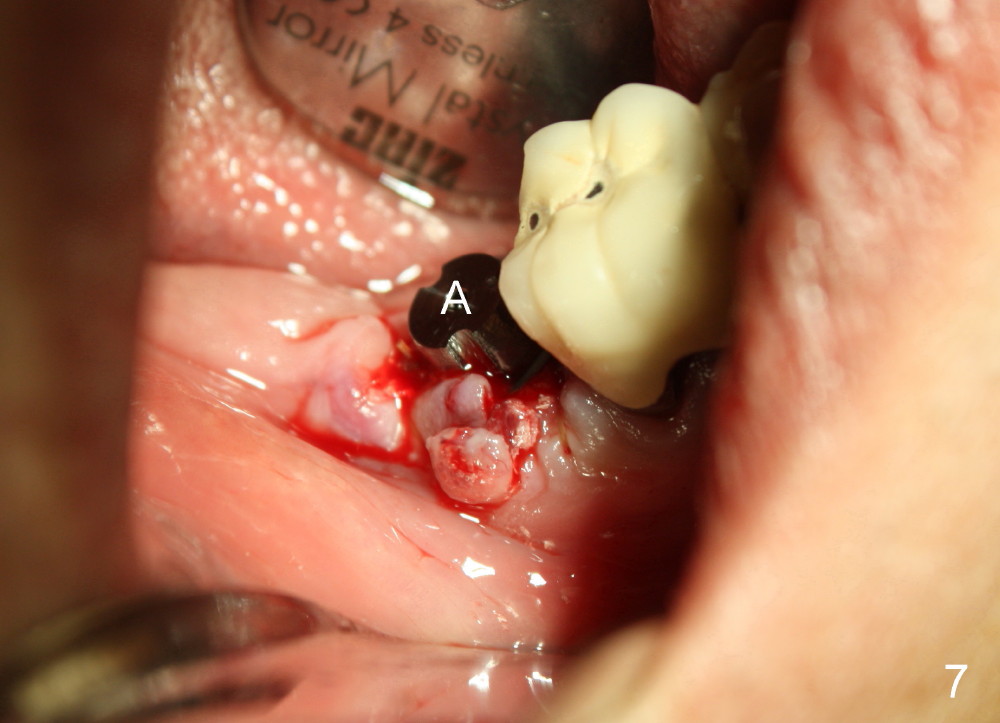

A 51-year-old man has experienced pain and swelling in the lower right 2nd molar for 7 months (Fig.1, P: post in the mesial root; <: gutta percha inserted into a buccal fistula). Fig.2 is taken immediately before extraction (<: purulent discharge from the mesiobuccal fistula) and immediate implant (Fig.3 implant design: 7x14 mm). A vertical root fracture is noted in the mesial root (Fig.4: lingual view). The septum is in fact absent, as compared to Fig.1. The mesiobuccal plate is low; the osteotomy starts lingual to the center of the socket. Fig.5 shows a 4.5x17 mm tap in place: approximately 3.5 mm in the new bone (~2.5 mm from the inferior alveolar canal). When a 7x17 mm tap (14 mm from the gingival margin) is placed in the socket, it looks relatively small. Fig.6 shows a 8x14 mm implant in place with a small gap distally. Mineralized cancellous allograft and Osteogen mixture is placed mainly buccally, followed by a thin strip of collagen dressing and sutures (Fig.7); an abutment (A) is placed to keep perio dressing in place. The perio dressing does not stay long. The buccal portion dislodges by itself 5 days postop. The lingual portion is removed in clinic. New dressing is going to be re-applied, because the buccal wound has not completely healed (Fig.8 <, albeit asymptomatic) with partial exposure of the bone graft (*). Why is the dressing lost so early? The abutment is not long enough; there is plenty of occlusal clearance (Fig.9 arrows). A longer abutment is used to increase mechanical retention for perio dressing (Fig.10). By the time the second perio dressing dislodges, the wound has healed (Fig.11, 13 days postop).